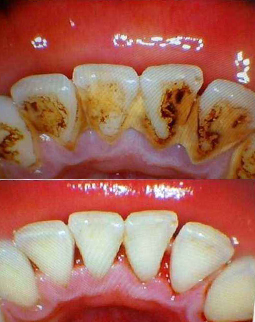

今天要做的第一件事,就是把半口的烤瓷牙冠全部拆掉,然后做了洗牙和局部上药消炎,等炎症控制好了以后,再说拔牙和种牙,医生跟我说,如果牙周炎症不做处理,口内的细菌太多拔牙后会出现感染,洁牙的过程很舒服,洁牙师和助理搭配,洗的很细心。身边不少朋友都担心洁牙会让牙齿变松,我到今天才明白,牙结石是造成我牙周炎症的主要原因,烤瓷牙是导致我根尖周炎的罪魁祸首,哎……强烈建议大家日常的口腔保健,1年两次洁牙还是要做起来的,积极的预防比后期的治疗更重要!洁牙完牙齿会更干净,口气也会清新不少。

题外话:上次提到洁牙,有收到不少私信,问我洁牙的一些问题,最常见的就是“洁牙会不会让牙缝变大”啊,其实以前我也担心这个问题,但后来医生跟我说,其实牙齿之前本来就有缝隙,只是当牙结石堆砌多了,把缝隙填满了,而且结石越来越多,还会把牙龈往下压,最后牙齿就会敏感了。所以,大家不要怕洁牙有副作用,选对医院就好了。